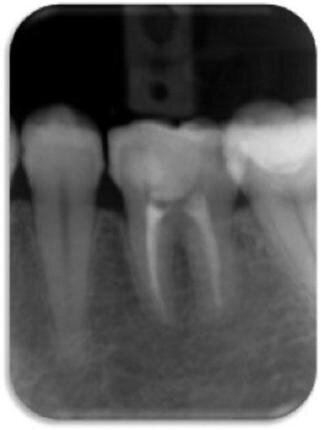

23-letni mężczyzna zgłosił się z bezobjawową zmianą próchniczą w zębie 36, która klinicznie i radiologicznie została rozpoznana jako martwica miazgi z rozległym AP (Ryc. 1). W wywiadzie pacjent nieobciążony. Jako preferowaną metodę leczenia wybrano przeszczep autogenny.

Dane uzyskane metodami radiograficznymi pozwalają na jedynie umiarkowane rozpoznanie, pozwalające odróżnić AP od torbieli korzeniowej.37,38 W opisanym przypadku stan kliniczny zęba 36 uzasadniał ekstrakcję wraz z usunięciem zawartości zmiany (Ryc. 1). Uwzględniając fakt, że przeszczep zęba uznaje się za przewidywalną opcję leczenia, tzw. ząb mądrości często jest najlepszą opcją dawcy.2,39 Niniejszy opis przypadku może stanowić potwierdzenie tej tezy, wraz z uzasadnieniem zabiegu chirurgicznego przeprowadzanego podczas jednej wizyty39,40 oraz istotności leczenia endodotycznego dla pozytywnego rokowania.6,41